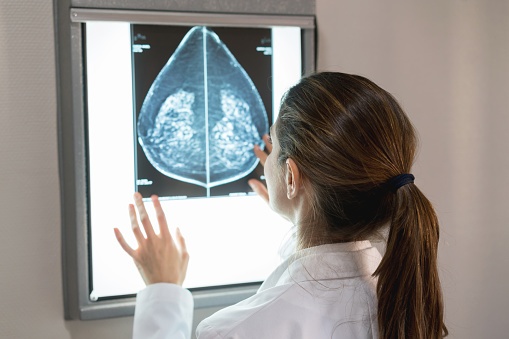

Researchers from Mayo Clinic Cancer Center suggest that advances in breast cancer prevention research have resulted in enhanced opportunities to modify breast cancer risk and potentially reduce breast cancer incident and death.

“It is prudent for health care providers to be knowledgeable about the benefits of assessing individual breast cancer risk, and counsel and implement risk-reducing strategies with their patients, says Sandhya Pruthi, M.D., a Mayo Clinic internist and author of the commentary via a press release.

According to Dr. Pruthi, evidence-based, risk-reducing strategies include lifestyle modification, preventive anti-estrogen medications, surveillance breast imaging and genetic testing. Women at high risk of harboring a hereditary breast cancer mutation should consider prophylactic surgery to reduce risk.